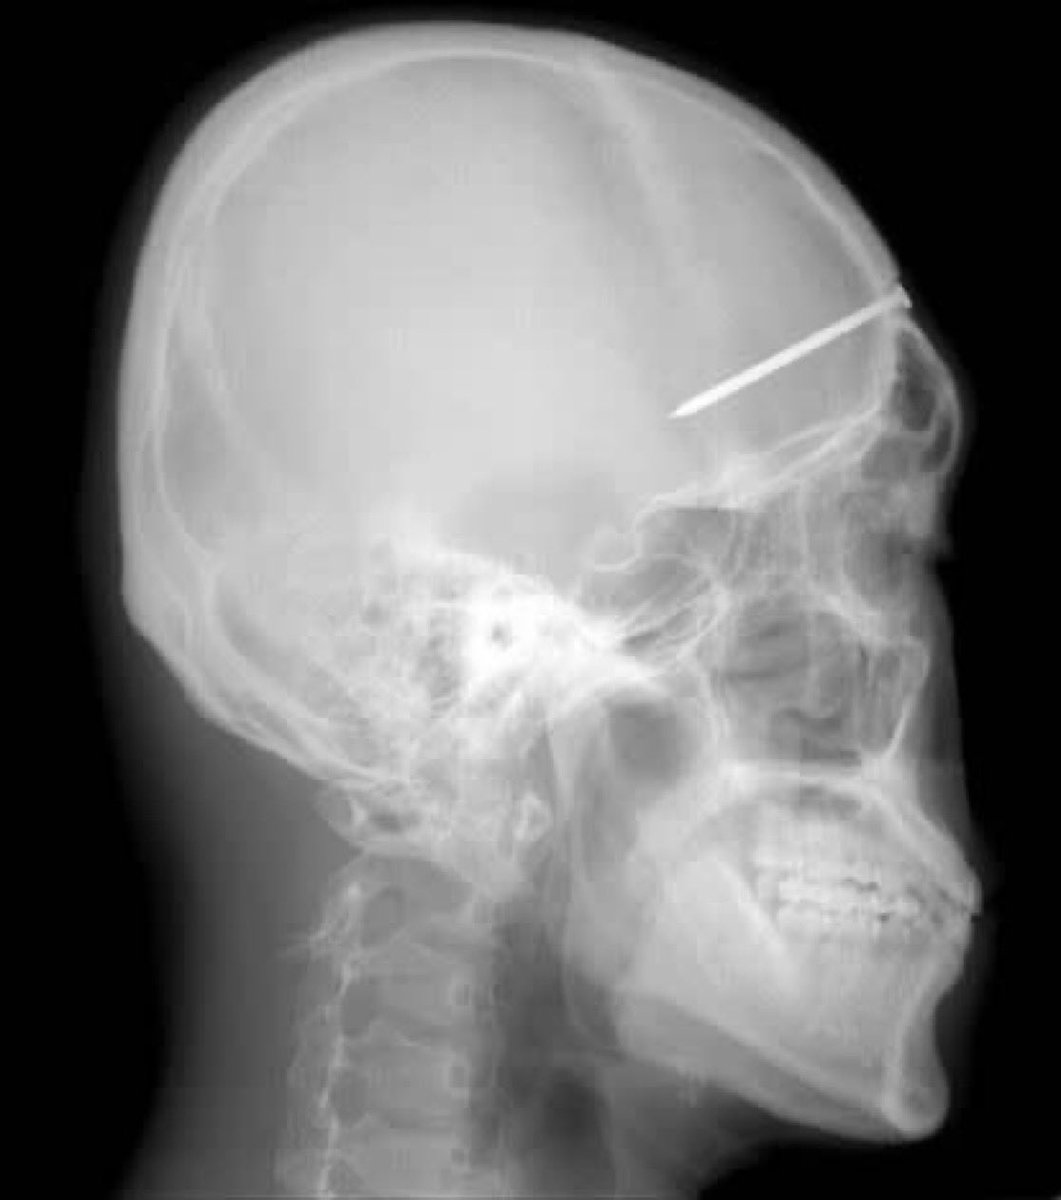

6. في عام 2004، أظهرت الأشعة السينية وجود مسمار طوله 5 سم في جمجمة مريض كوري جنوبي. كان الرجل يعاني من صداع شديد. اكتشف الأطباء في أحد مستشفيات سيول المسمار الذي يعتقدون أنه كان هناك لمدة أربع سنوات بعد وقوع حادث غير معروف للمريض.